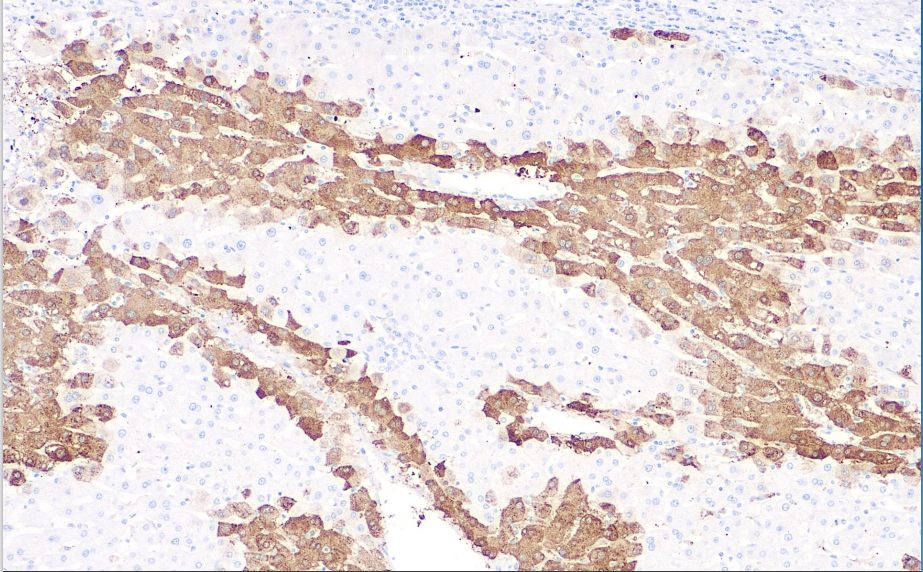

Positive control: Liver

In mammalian livers, glutamine synthetase (GS) catalyzes the synthesis of glutamine from glutamate and ammonia. Glutamine, as the active product of GS, is the primary energy source for tumor cells. Studies on the development of liver cancer have found that GS-positive tumor cells are believed to originate from GS-positive hepatocytes. In normal livers, GS is primarily expressed in hepatocytes surrounding the portal vein, with minimal involvement of intermediate and peripheral cells. However, in hepatocellular carcinoma, most tumor cells exhibit diffuse expression of GS. In non-malignant liver cell lesions, such as degenerative nodules, the positive expression rate is below 50%, while in early-stage hepatocellular carcinoma and well-differentiated hepatocellular carcinoma, the positive expression rate exceeds 60%. Therefore, diffuse positive expression compared to negative or focal expression may indicate early-stage or well-differentiated hepatocellular carcinoma, while the latter may indicate liver degenerative nodular lesions.

Glutamine Synthetase antibody reagents can specifically bind to Glutamine Synthetase molecular antigens. Immunohistochemistry kits containing Glutamine Synthetase antibody reagents are suitable for the precise diagnosis of hepatocellular adenoma and liver cancer.